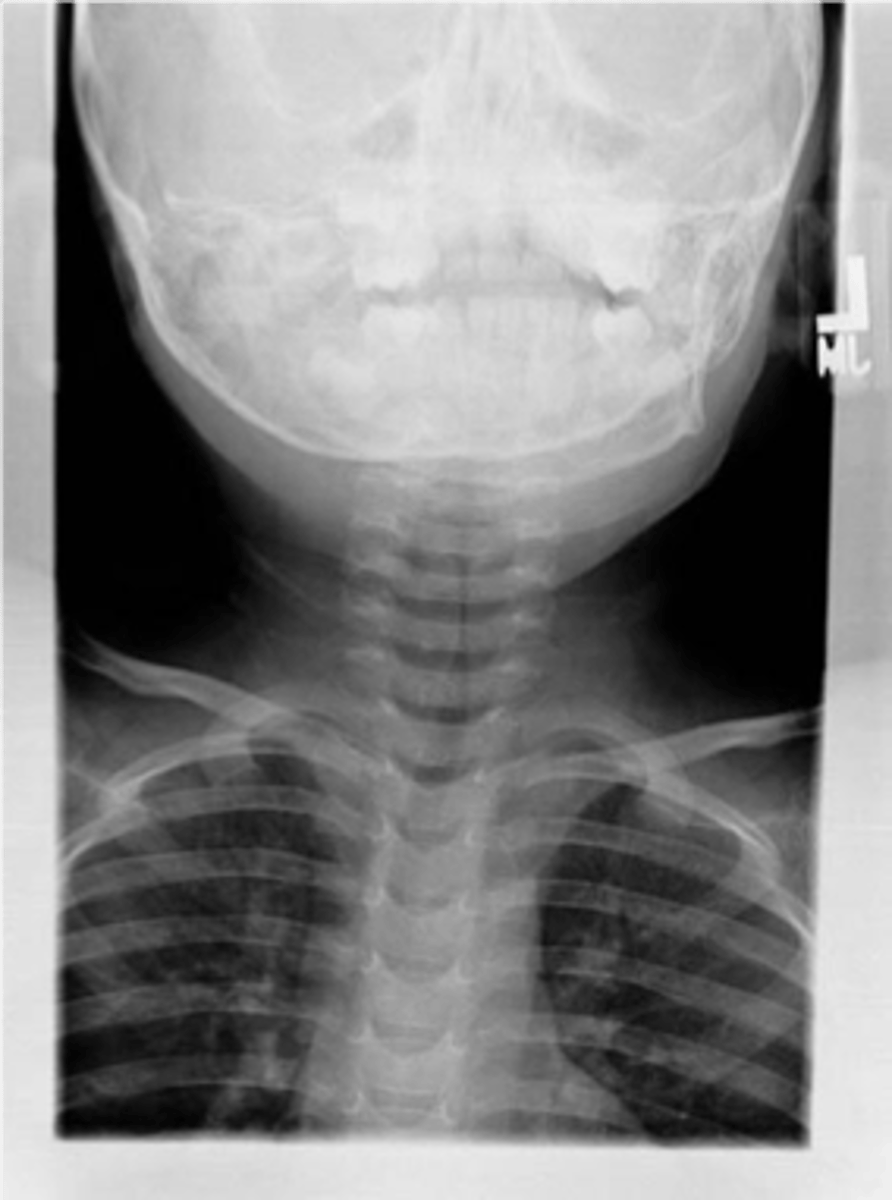

Epiglottitis (thumb sign)

knowt flashcard image

steeple sign (croup)

Croup

Steeple sign- group